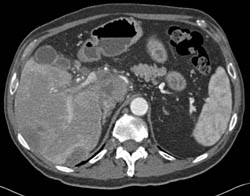

Focal Nodular Hyperplasia (FNH)